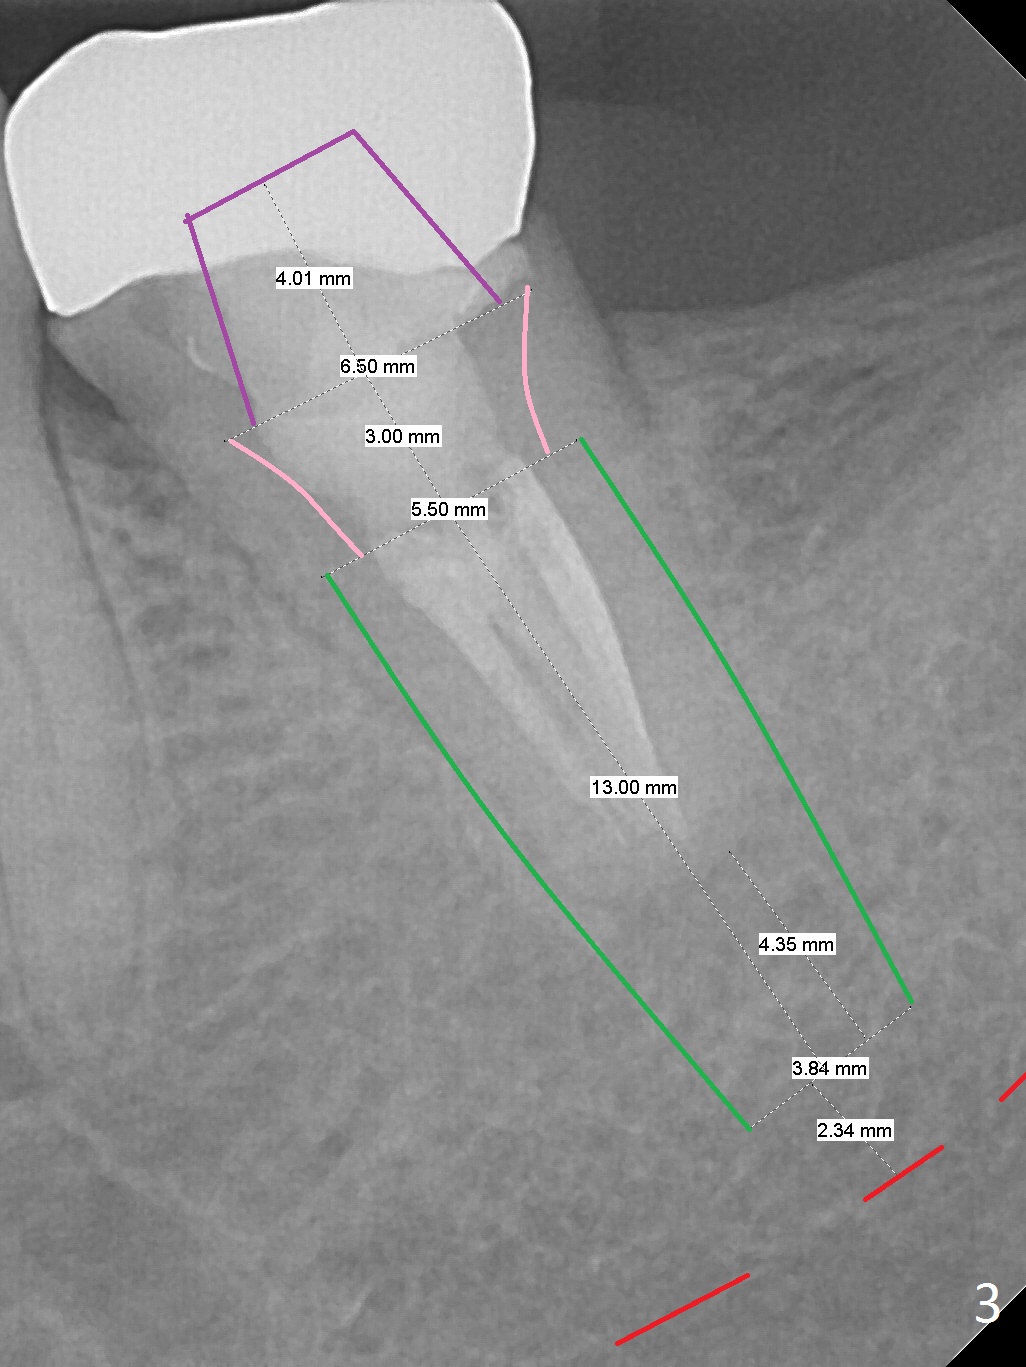

A 45-year-old man has had trouble with the tooth #18 for long time. First, the tooth needed RCT and crown retreatment several years ago (Fig.1). Now there is 2nd caries underneath the crown (Fig.2). After extraction and No Antibiotic, an IBS or Tatum implant will be placed (Fig.3).